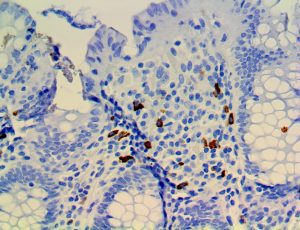

Clinical and laboratory manifestations of HLH include fever, enlarged liver and/or spleen, neurologic dysfunction, coagulopathy, liver dysfunction, cytopenias (i.e., low levels of erythrocytes, leukocytes, and/or platelets), hypertriglyceridemia, hyperferritinemia, hemophagocytosis, and eventually diminished NK cell activity as the immune system becomes progressively paralyzed. HLH can be familial (primary HLH) or secondary to another disease process (sHLH), such as rheumatic disease, in which it is referred to as macrophage activation syndrome (MAS, characterized by elevated ferritin).

This activation induces inflammatory monocytes to highly express IL-6, starting a localized and then systemic cascade effect that results in hyperproduction of IL-6, which accelerates the inflammatory process. Because IL-6 also increases vascular permeability, excessive levels cause blood vessels to become very leaky. This, along with clotting factors released from vascular endothelial cells, stimulates the coagulation cascade, resulting in microthrombosis (tiny clots), which leads to ischemia and tissue death of the kidney, intestines, heart, liver, brain and extremities.